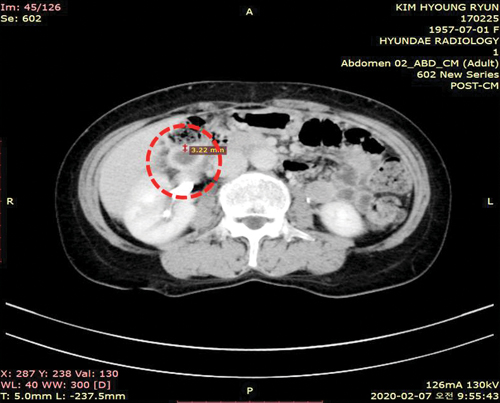

±èÇü·Ã ±Ç»ç (65¼¼, 2´ë´ë 12±³±¸)

Áö³ 1¿ù 23ÀÏ Àú³á, º¹ºÎ¿¡ ÅëÁõÀ» ´À²¼´Âµ¥ 25ÀÏ¿¡´Â ÅëÁõÀÌ ´õ¿í ½ÉÇØÁ® ¹ã»õ ¹è¸¦ ¿òÄÑÀâ°í ÀáÀ» ¸ø ÀÌ·ç¾ú½À´Ï´Ù.

ÃÊÀ½ÆÄ °Ë»ç¸¦ ÇØ º¸´Ï '±Þ¼º ´ã³¶¿°'(´ã¼®, ¼ö¼ú ÈÄ ÇùÂø, Á¾¾ç µîÀÇ ¿øÀÎÀ¸·Î ÀÎÇØ ¿ÏÀü ȤÀº ºÒ¿ÏÀüÇÑ ÇùÂøÀÌ ¹ß»ýÇÏ¿© ´ã°üÀ» ÅëÇØ Àå³» ¼¼±ÕÀÌ ´ãÁó ³»¿¡¼ Áõ½ÄÇÏ¸é¼ ´ã³¶¿¡ ¿°ÁõÀ» ÀÏÀ¸Å°´Â Áúȯ)À̾ú½À´Ï´Ù.

´ã³¶ º®ÀÇ µÎ²²°¡ 1.78cm·Î, ÀÇ»ç´Â ´çÀå ¼ö¼úÇØ¾ß ÇÏ´Â ¸Å¿ì À§±ÞÇÑ »óȲÀ̶ó°í ¸»Çß½À´Ï´Ù. ÇÏÁö¸¸ Àú´Â Çϳª´Ô²² ¹ÏÀ½À¸·Î Ä¡·á¹Þ°í ½Í¾ú±â¿¡ 28ÀÏ ¸¸¹Î±âµµ¿ø Áýȸ¿¡ Âü¼®Çß½À´Ï´Ù.

ÀÌÈÄ ´çȸÀå ÀÌÀç·Ï ¸ñ»ç´Ô²²¼ ±âµµÇØ ÁֽŠ±Ç´ÉÀÇ ¼Õ¼ö°Ç(Çà 19:11~12)À¸·Î À̺¹´Ô ¿øÀå´ÔÀÌ Àú¸¦ À§ÇØ ¶ß°Ì°Ô ±âµµÇØ ÁÖ½Ã´Ï Ãæ¸¸ÇÔÀÌ ÀÓÇß°í, 29ÀÏ ÃÊÀ½ÆÄ °Ë»ç °á°ú ´ã³¶ º®ÀÇ µÎ²²°¡ 0.5cm·Î ÁÙ¾î ÀÖ¾ú½À´Ï´Ù.

±×¸®°í 2¿ù 7ÀÏ º´¿ø¿¡ °¡¼ °Ë»çÇÑ °á°ú, ´ã³¶ º®ÀÇ µÎ²²°¡ 0.3cm·Î °ÅÀÇ Á¤»óÀÌ µÅ ÀÖ´Â °ÍÀ» È®ÀÎÇÒ ¼ö ÀÖ¾úÁö¿ä. ÇÒ·¼·ç¾ß!

ÃÊÀ½ÆÄ&CT »çÁø

±âµµ ¹Þ±â Àü - ´ã³¶ º®ÀÇ µÎ²²°¡ 1.78cm·Î Ä¿Á® ÀÖ¾î ´ã³¶¿° ¼Ò°ßÀ» º¸ÀÓ.

±âµµ ¹ÞÀº ÈÄ - ´ã³¶ º®ÀÇ µÎ²²°¡ 0.3cm·Î °ÅÀÇ Á¤»ó ¼Ò°ßÀ» º¸ÀÓ.